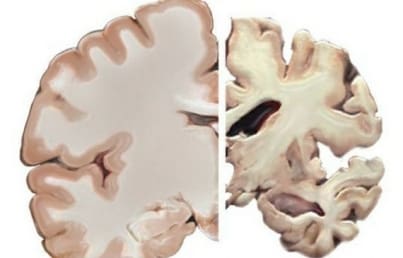

México.-Tras padecer Covid-19, algunos pacientes han reportado secuelas neuropsiquiátricas como delirios, agitación, encefalitis, depresión y ansiedad; según especialistas esto se debe a que el coronavirus entra al Sistema Nervioso Central.